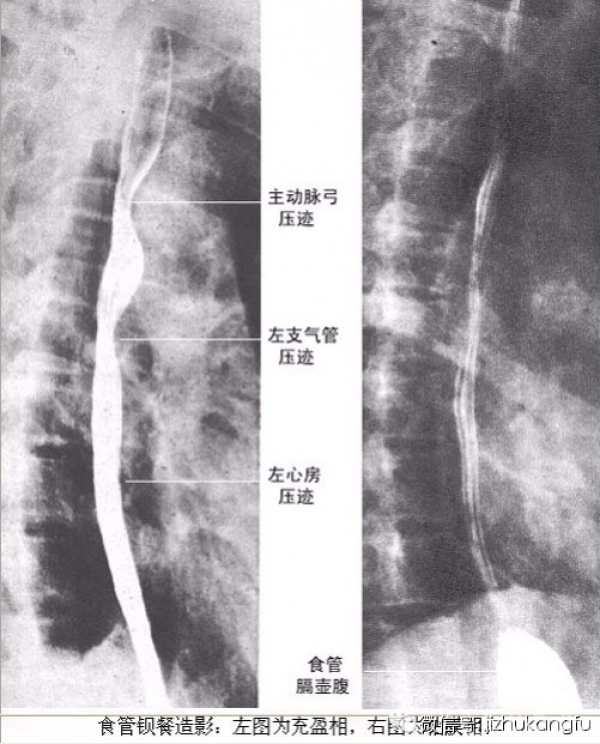

2颈椎

4内脏器官

2脊柱